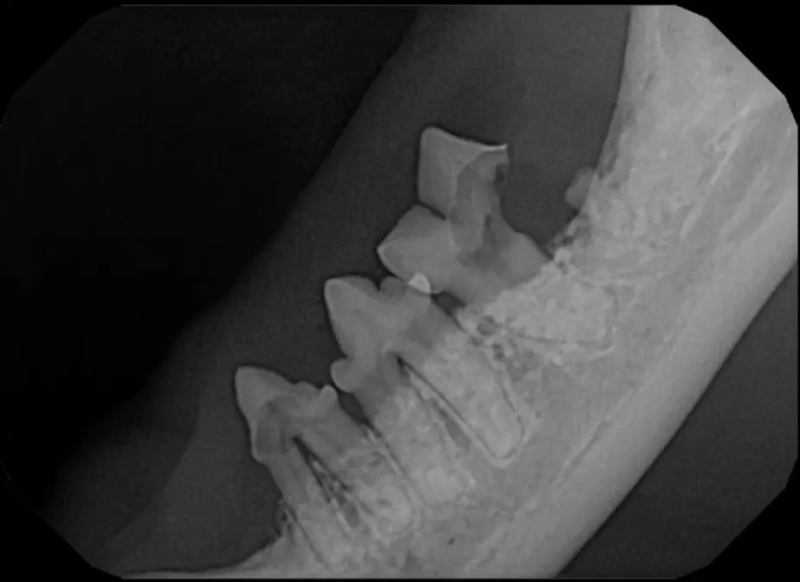

Cone Beam Computed Tomography

The Center now provides advanced imaging via cone beam CT. Cone beam CT is excellent for visualization of bony structures of the skull, nasal cavity, teeth, and ears. Cone beam CT is especially helpful for diagnosing dental disease and evaluation of jaw fractures. It can also be useful for evaluating the sinuses and tympanic bulla. Cone beam CT can be used in conjunction with nasal biopsy and culture to evaluate nasal discharge whether chronic or acute.